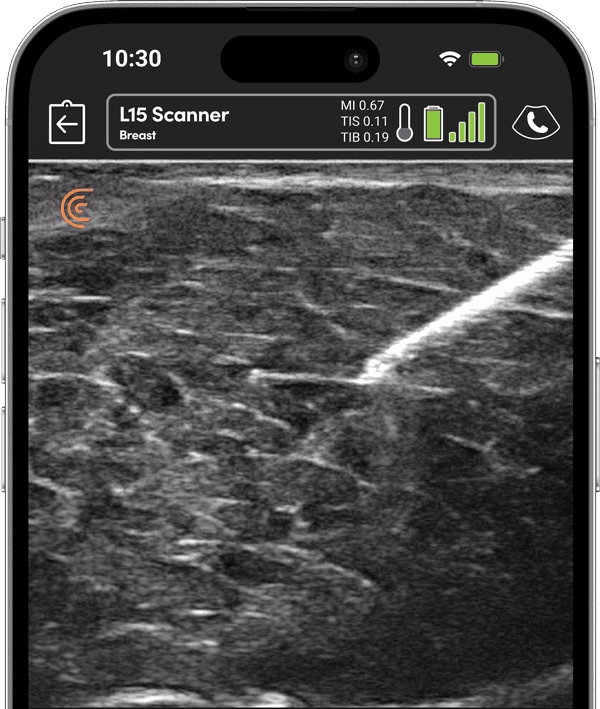

フィラーや脂肪を正確に注入するため、注射針の視認性を高め、注入精度を向上。

Salzman医師は、この両側乳房のフォローアップ検査で、片側のインプラントの破損と、もう片側のインプラントの反転を検出する。

術前の超音波ガイド下PECブロックは、豊胸手術後の痛みと麻薬の消費を減らすことが示されています。クラリスの高解像度超音波を使用して、大胸筋と小胸筋の間の筋膜の位置を確認し、正確な注射のために針を誘導します。麻酔薬の正確な配置を確認するために筋肉の分離を見ます。